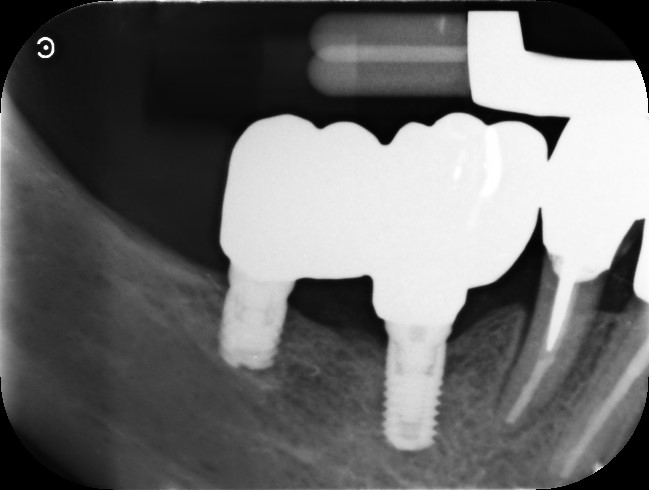

A sei mesi dalla consegna delle corone è stata eseguita un Rx endoorale di controllo da cui si evidenziava una buona stabilità dell’osso marginale (Fig. 11).